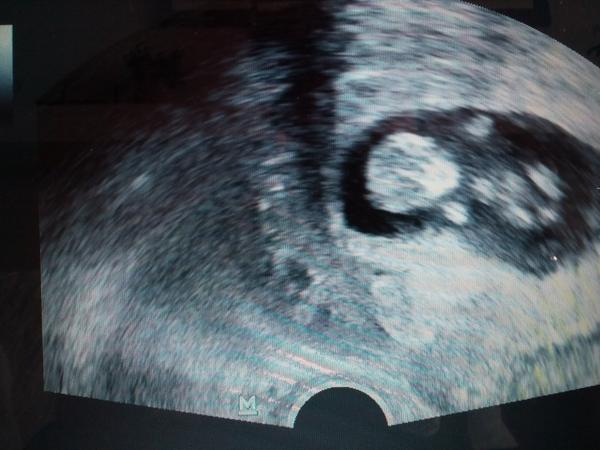

@evulik1111 ahojky 🙂 dneska som 10tt+4 😉 bola som na sone babenko nam rastie krasne meral od hlavicky po kostrc len sa stocilo ☹ cize priblizne mame teraz 3,8cm ale kedze sa cele skrutilo tak povedal ze ta velkost je len orientacna kedze sa nechcelo dat odmerat a ze je vacsie len s nim nic neurobi 🙂 strasne sa hybe 😀 ja sa tesim hlavne ze rastie a plava a ze mu/jej je dobre a nic nechyba 🙂 fotku som odfotila z videa lebo mi dal video aj spredtym na usb a dal mi aj dnesne video a fotit sa dobre nedalo lebo plavalo 😀 ruckami aj nozkami hybalo jak divoch 😀 kazdy jeho mm milujem :-* cize maly plavec je z neho/nej 🙂 takze ako som pisala sa to otocilo a teraz mas vacsie babenko ty 😉 kazde babenko inak rastie a pribera 🙂 moje ma nuti malo jest 😀 strasne sa tesim :-* prvu poradnu mam koncom augusta ,knizku mi uz vypisali ale daju mi ju az na tej poradni a vtedy idem na moc a aj na krv 🙂